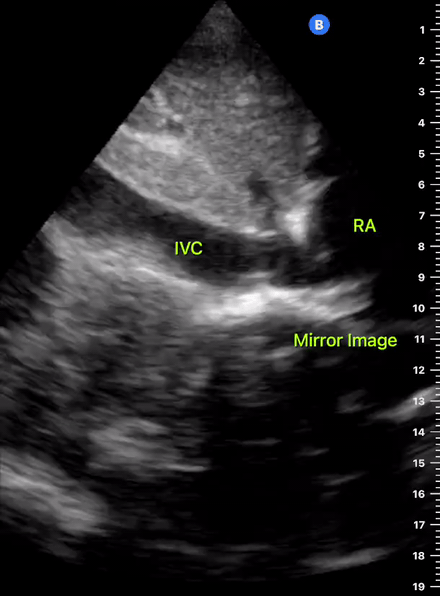

The IVC diameter changes depending on intravascular volume status, and normally, the IVC collapses during spontaneous inspiration. Therefore, the IVC diameter represents a non-invasive method for estimating central venous pressure (CVP). The evidence suggests that in spontaneously breathing patients, there is a good correlation between the sonographic estimation of CVP and values measured with invasive methods (2). IVC filling and CVP, however, allow only a rough correlation with volume status, and the sonographic estimation of preload should at least include the assessment of the LV and the Lung. Thus, it is better to think of IVC filling as an indicator of fluid tolerance, instead of a determinant of fluid responsiveness (6).

IVC exploration is best from the subxiphoid approach with longitudinal and transverse images. The IVC should be assessed in terms of overall size and collapsibility. The diameter is typically measured at its largest (end of expiration) at 1-2 cm distal to where the hepatic veins join the vena cava. An IVC diameter of ≥ 2 cm, especially with minimal or no collapsibility, is considered plethoric and correlates with increased RA pressure. An IVC of < 1 cm, particularly with complete collapse, is considered flat and indicates low preload and potential fluid responsiveness. An IVC diameter between 1 and 2 cm is typically normal.

PITFALLS

In a long-axis view, beware of not sliding off the centre of the vessel, as this will underestimate the size of the IVC and overestimate its collapse. Obtaining long and short axis views may help avoid this pitfall. Another mistake is confusing the descending aorta for the IVC, particularly when scanning in long-axis. Although the IVC may appear to pulsate, the aorta has a thicker wall, and its position is to the patient’s left. Following the IVC upwards will reveal the hepatic veins junction and the entrance to the RA, while the aorta will travel behind the heart. The IVC moves both anterolaterally and craniocaudally with inspiration, and this should be considered during visualization or measuring. For this very reason, measuring in M-mode is not recommended as it would not be accurate.

SHOCK

In a shocked patient, a flat or highly collapsible IVC correlates well with low preload estates (hypovolaemia, haemorrhage, sepsis). Yet by itself, a small IVC is not enough to define low preload and could also represent a normal finding.

Conversely, a distended, not collapsing IVC suggests distal obstruction in a shocked patient. Potential causes include LV failure, massive PE, tension pneumothorax and cardiac tamponade. Nonetheless, there are other causes of elevated cava / RA pressure, such as chronic pulmonary hypertension.